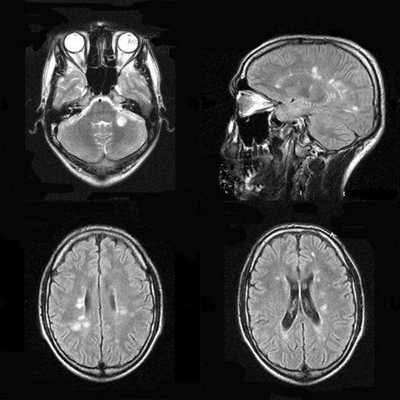

(а) Бесконтрастная КТ, аксиальный срез: у новорожденного с ВПГ-2-энцефалитом определяются протяженные зоны снижения плотности серого и белого вещества. У 27% инфицированных новорожденных признаков заболевания при первичной бесконтрастной КТ не наблюдается.

(б) МРТ, ДВИ, аксиальный срез: у двухнедельного ребенка с судорожным синдромом и выбуханием родничка визуализируется распространенное ограничение диффузии в области структур серого и белого вещества без четкой локализации ЕЯ. Были выявлены увеличение IgM и положительный результат ПЦР против ВПГ. ДВИ имеет большое значение в ранней диагностике этого состояния.

(а) МРТ, Т2-ВИ, корональный срез: у младенца, у которого в перинатальном периоде был диагностирован ВПГ-2-энцефалит, определяются распространенная кистозная э нцефаломаля-ция с выраженным расширением боковых желудочков заместительного генеза.

(б) Патологоанатомический макропрепарат головного мозга новорожденного, корональный срез: определяются изменения, вызванные вертикально переданной ВПГ-2-инфекцией, включающие расширение желудочковой системы, кистозную энцефаломаляцию и отсутствие нормального рисунка извилин коры. Внутриутробную передачу имеют около 5% всех ВПГ-2-инфекций у новорожденных.